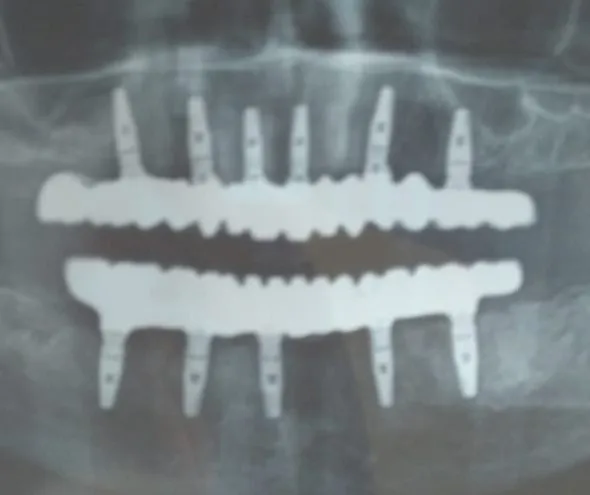

- As part of the full mouth rehabilitation, 11 dental implants were placed using precision-guided techniques (6 upper, 5 lower).

- Implant positions were strategically chosen to maximize stability and ensure even load distribution.

- A minimally invasive approach was adopted to enhance healing and reduce discomfort.

- After a healing period, custom-designed zirconia prosthetic teeth were fixed, ensuring natural aesthetics and durability.